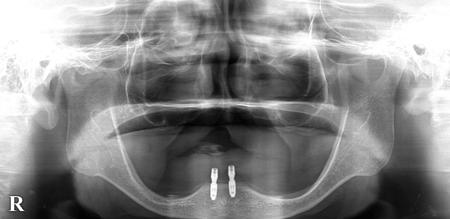

2025.10.0290代男性「他院にて下顎作製したが合わず痛い。食事がとれない。」下顎の前歯部にインプラントを2本埋入し、しっかりと噛めるようになった症例